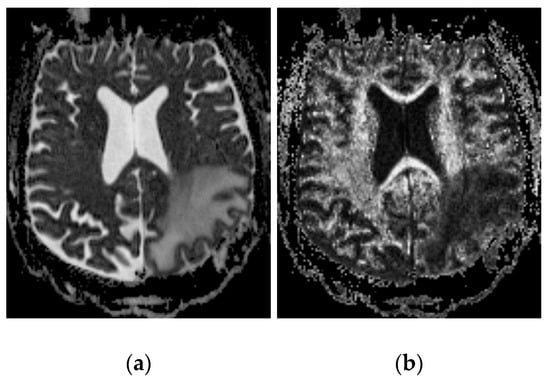

2.2.2. Imaging Protocols

2.2.3. Concentration Measurement

2.2.4. Distribution Volume Measurement